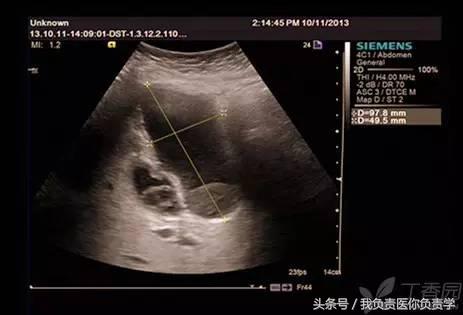

患者男,64岁,因右上腹疼痛半月余就诊。查体发现右上腹部轻压痛,无发热。超声检查所见如下:

图4和5为局部放大图像,可见胆囊与囊性回声区间可见直径约2mm的通道